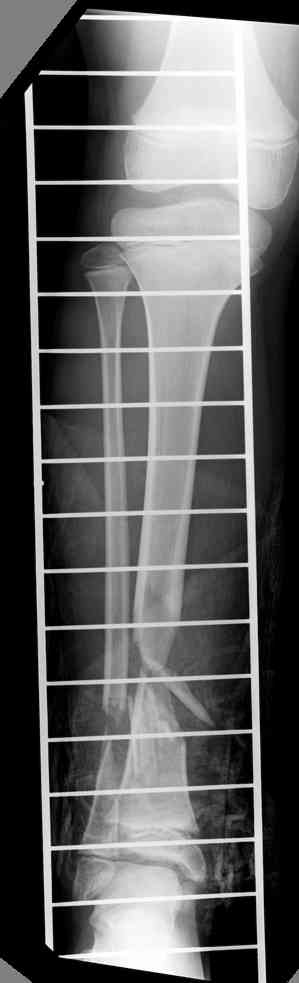

Another choice is simply perform shortening + posterior angulation with Ilizarov or TSF , than gradual correction of the angulation.After all apply third ring on the proximal tibia and start lengthening.

We had recently similar case in 14 years old boy with 45 mm bone defect after open tibial fracture.Boy doing excellent .This technique is not new, Sasha Lerner did it in Rambam , Rozbruch wrote also.

Действительно, если есть длинная косая линия на проксимальном отломке, это жалко будет не использовать. Можно сделать коррекцию угла не обратным разведением фрагментов, а оставить их в контакте, и сделать кортикотомию проксимальнее на 2-3 см. Можно и сейчас отсечь такой фрагмент и транспортировать его с разворотом. Наверно, вариант с ангуляцией более технологичен.

Было бы это подальше от сустава...